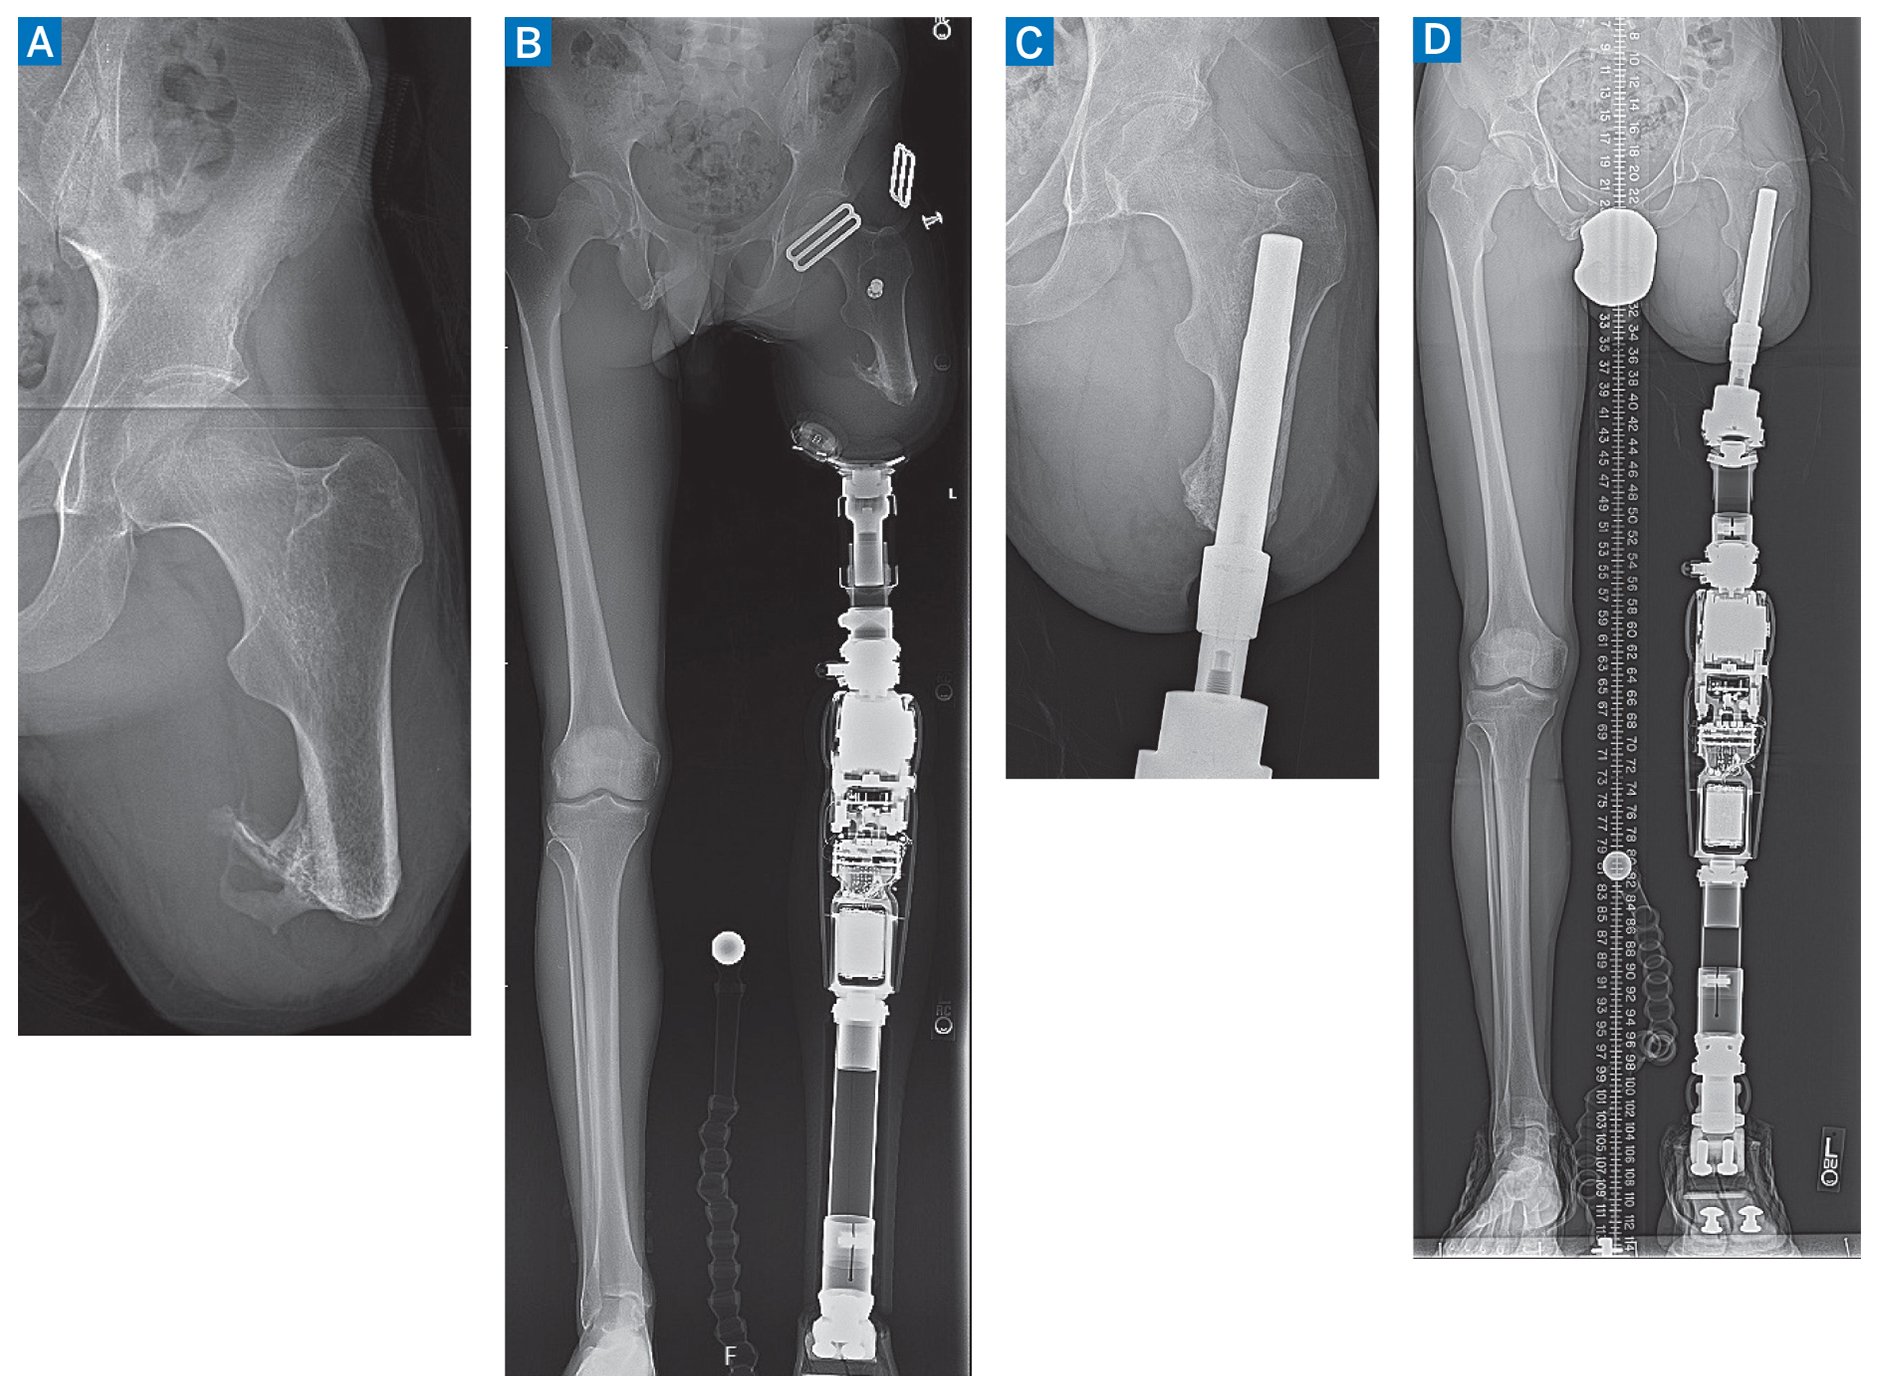

Physical examination revealed a left femur that measured 10 cm from groin to limb’s end, full strength, slight abduction and flexion contractures, and healthy skin that was not excessive (Fig. 1). His gait featured a short stance phase on his amputated side, with side-to-side sway and left-sided pelvic elevation to maneuver the prosthesis. Radiographs identified 6.5 cm residual femur beyond the lesser trochanter with slight distal heterotopic ossification and no hip joint arthrosis (Fig. 2). A long standing radiograph identified features typical of transfemoral amputation: a net femur abduction of 21° (femur anatomic axis 14° abduction vs the right’s normal 7° adduction), a medial mechanical axis deviation of 28 mm, and a prosthesis that was too short by 12 mm (imparting a 5° pelvic obliquity) to facilitate swing-through (accommodating the prosthetic limb’s sag during gait).

Figure 2: Preoperative radiographs (A, B) identify the amputated femur with joint abduction contracture and mechanical axis deviation. His postoperative radiographs (C, D) identify a stable osseointegrated prosthesis, neutral mechanical axis, and level pelvis.

The patient has made excellent progress through 18 months of follow-up. His gait is nearly completely natural. The stoma surrounding the transcutaneous implant is healthy (Fig. 1). Radiographs (Fig. 2) identify the osseointegrated prosthesis is stable with the long standing radiograph showing his femur has identical alignment to his unaffected side. His leg lengths have minimal difference which achieves a level pelvis, and his mechanical axis is directly through the knee joint. His mobility and enjoyment of life have markedly improved.